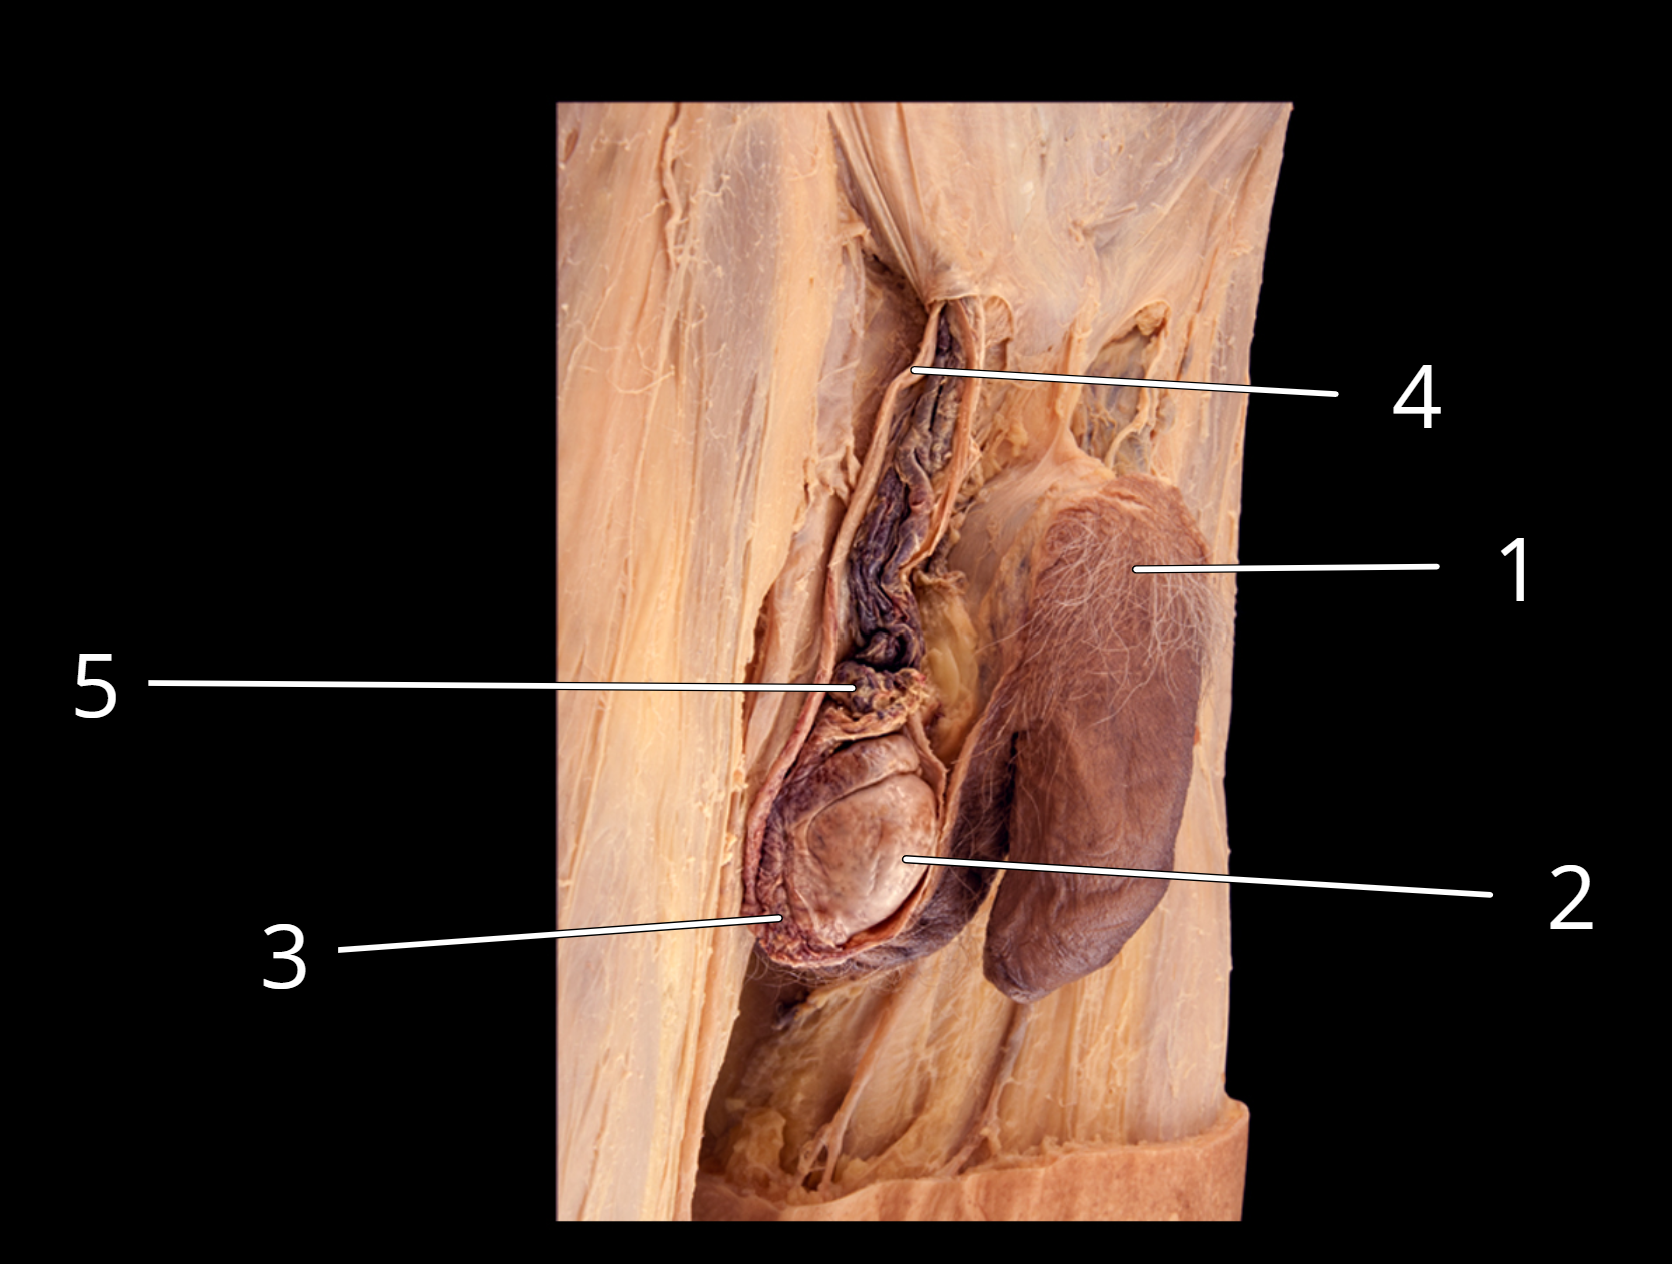

Penis and testis, lateral view

1. Penis

2. Testis

3. Epididymis

4. Ductus deferens

5. Testicular artery and pampiniform plexus of veins